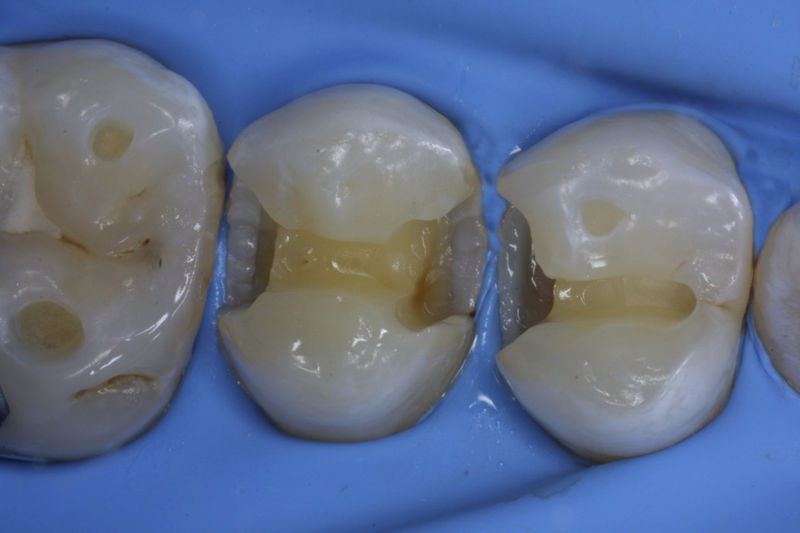

Restauraciones fabricadas en el laboratorio con materiales estéticos, los cuales cubren de manera parcial dientes posteriores. Se utilizan primariamente para restaurar dientes con caries, fracturas y/o defectos amplios. Para poder enviar el caso al laboratorio se toman impresiones utilizando materiales de impresión o técnicas modernas digitales.

Restauraciones fabricadas en el laboratorio con materiales estéticos, los cuales cubren de manera total dientes anteriores y posteriores. Se utilizan primariamente para restaurar dientes con caries, fracturas y/o defectos amplios, así como soportes de puentes. Para poder enviar el caso al laboratorio se toman impresiones utilizando materiales de impresión o técnicas modernas digitales.

Disciplina fundamental de la Odontología enfocada en el diagnóstico, prevención y tratamiento restaurador de las piezas dentales que han sufrido daños. Su objetivo principal es devolver al diente su equilibrio biológico, funcional y estético cuando su integridad ha sido alterada. Resinas directas, incrustaciones, coronas.